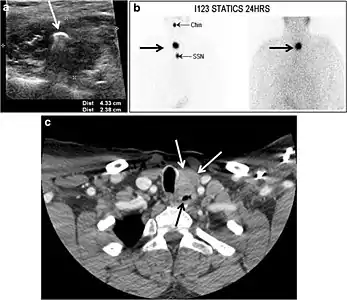

Ectopic thyroid tissue may be detected in the tongue near the foramen cecum (90%) and along the midline between the thyroid isthmus and posterior tongue, lateral neck, mediastinum, and oral cavity. The most frequent location is the base of the tongue (Figs. 16, 1717 and and18).18). In 70% of cases, the ectopic thyroid is the only functional thyroid tissue present in the body (Fig. 18).[1]

Ectopic thyroid tissue lateral to the orthotopic midline location is rare. The exact anatomical definition of this rare entity is debated in the literature. To avoid confusion, some authors define a lateral neck ectopic thyroid as any thyroid tissue superficial to the strap muscles with no midline continuity. The majority of lateral thyroid ectopia cases have been reported as lesions closely related to the strap muscles. There are few reported cases of ectopic lateral thyroid tissue in the submandibular region, jugulodigastric region, or within the parotid gland substance (Fig. 17).[1]